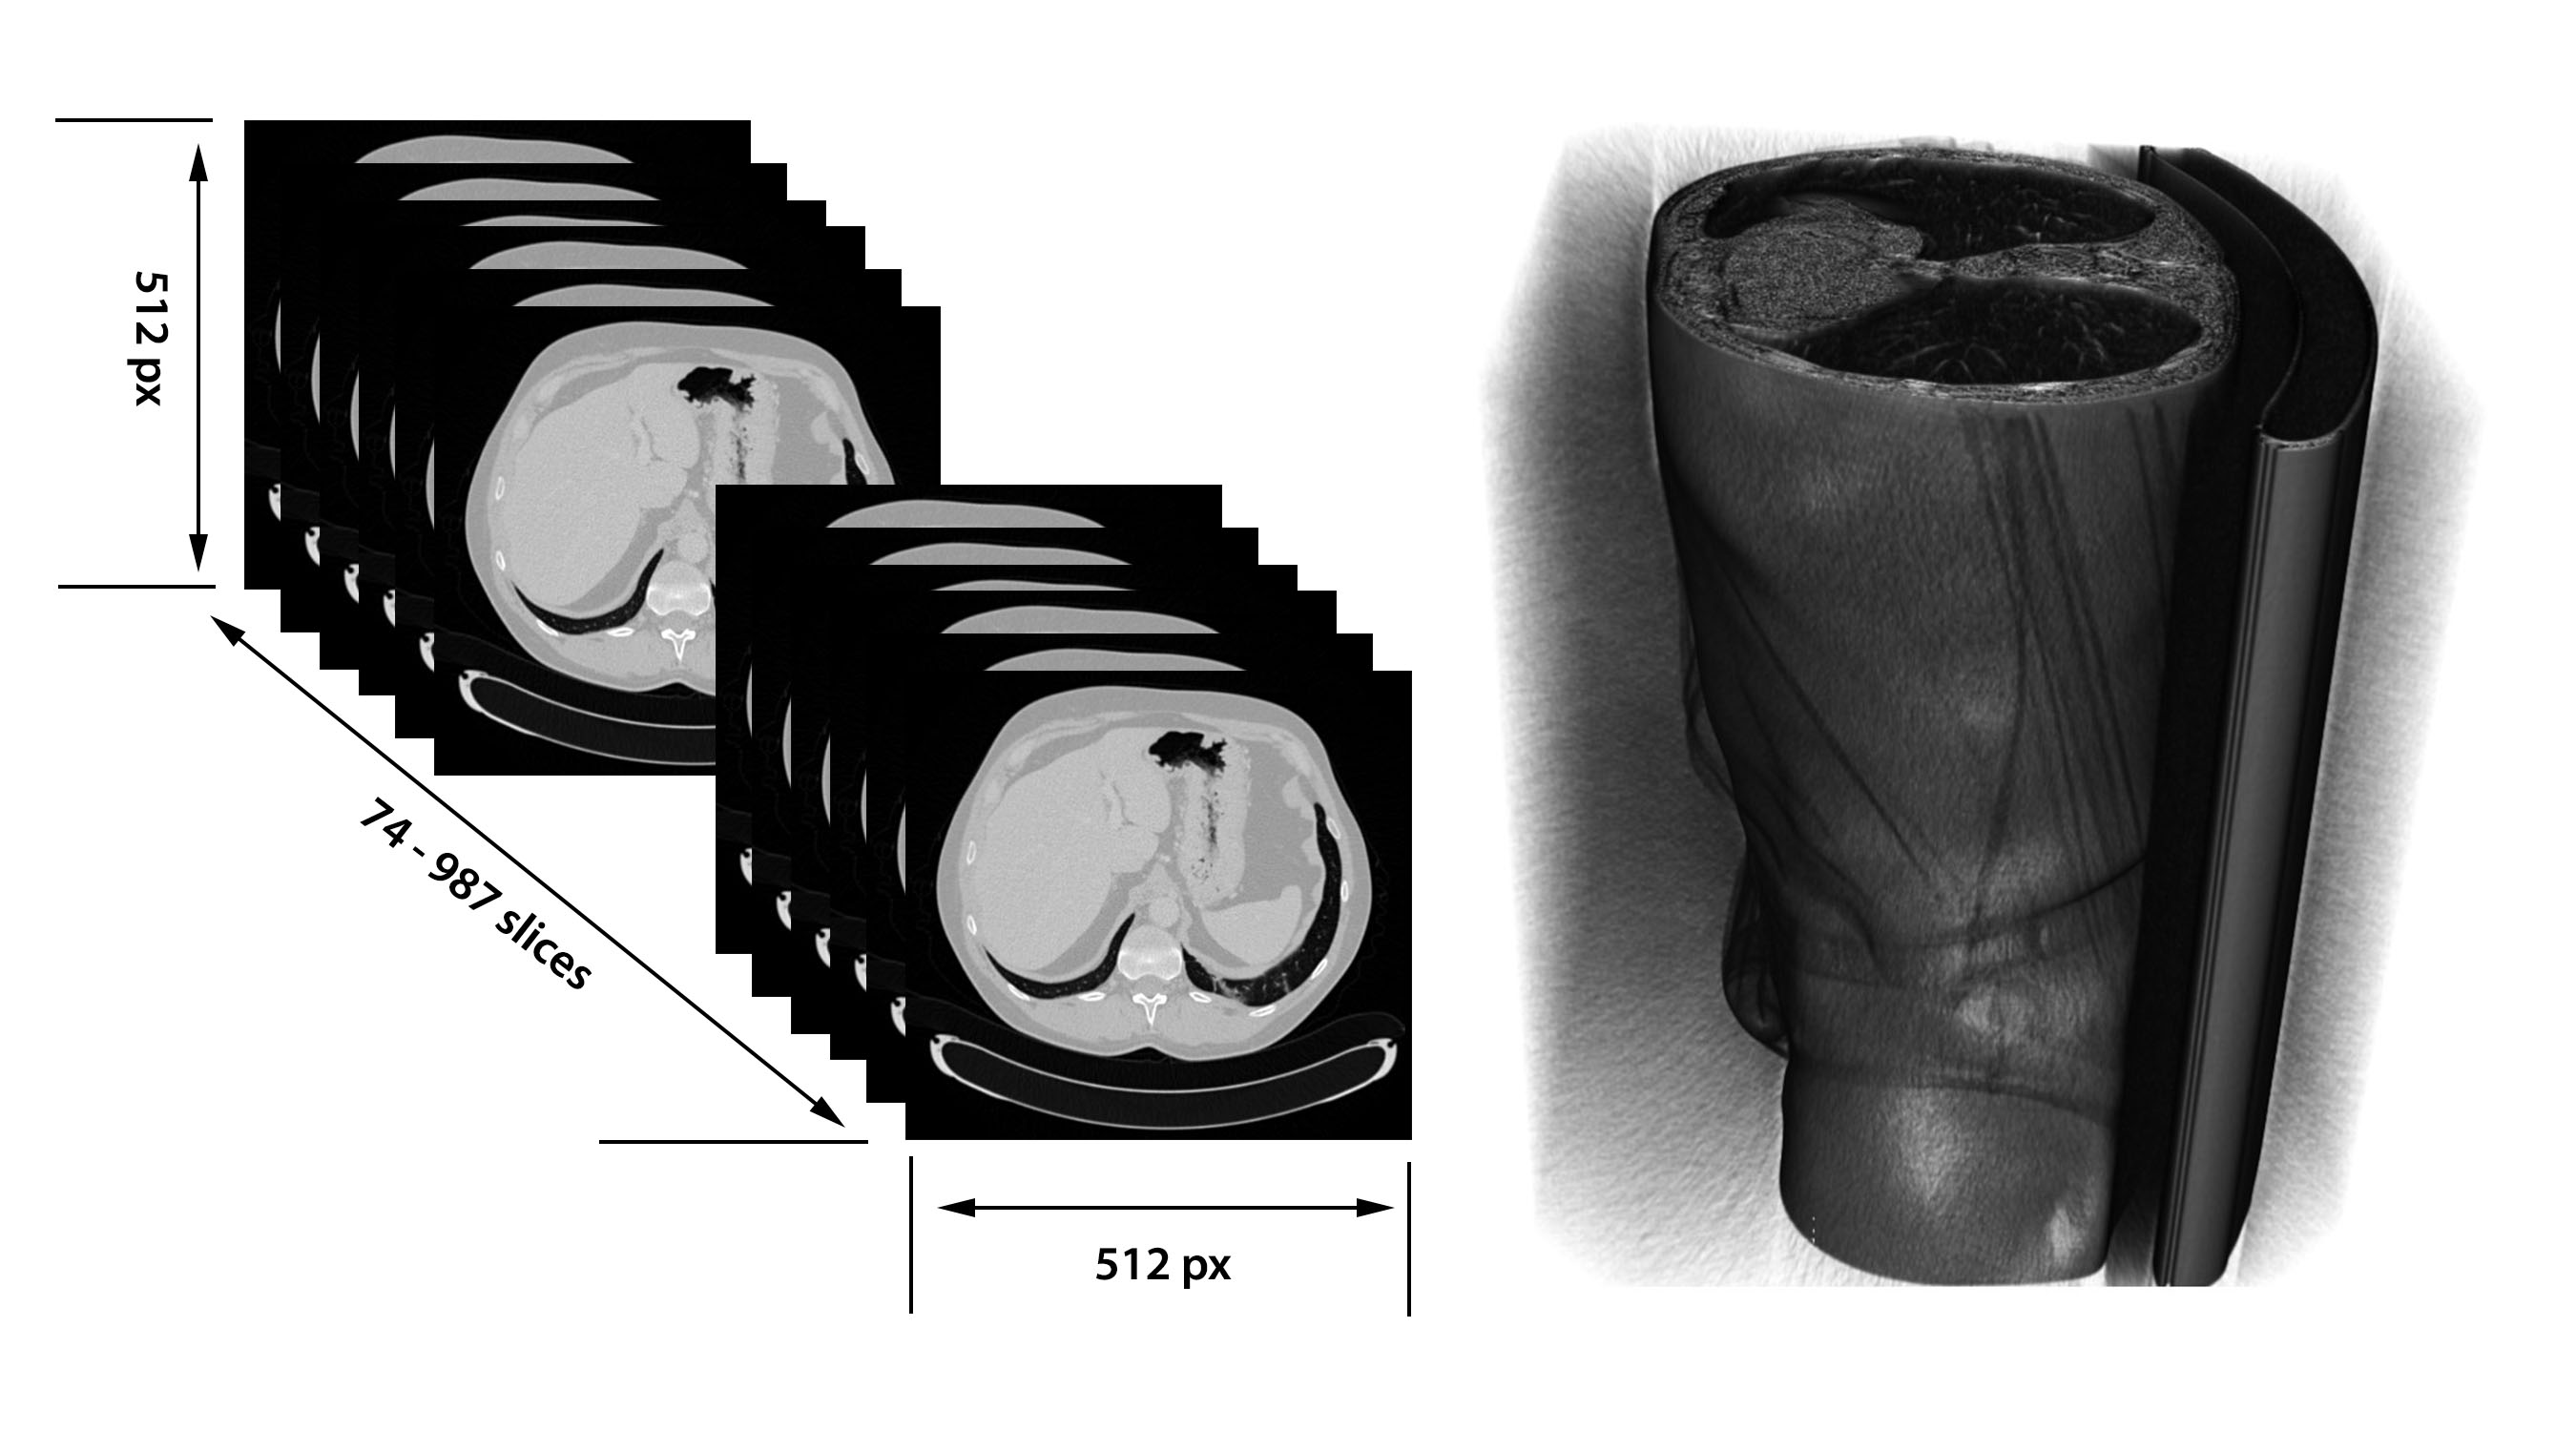

The liver dataset used to train the algorithm is obtained from the Liver Tumor Segmentation challenge (LiTS) [10], opened in 2017 for a ISBI workshop (International Symposium on Biomedical Imaging Conference). The challenge reopened once more during 2017, for a MICCAI workshop (Medical Image Computing and Computer Assisted Interventions Conference). The set consists of 131 CT scan volumes for training and 70 volumes for test. The file format is Neuroimaging Informatics Technology Initiative (Nifti), a format usually used for biomedical imaging. The file extension is ".nii", and it stores one volume per file. For encoding and decoding the file, a Matlab extension is used. Because each volume consists of multiple slices (74 up to 987 slices for each volume), the whole set includes in total 58,638 images. Each image is 512x512 pixels. The 3D image structure is depicted in Figure 3.9.

For the current task, the training set of 131 volumes was split into 80% training and 20% validation, i.e. 105 training volumes and 26 validation volumes.